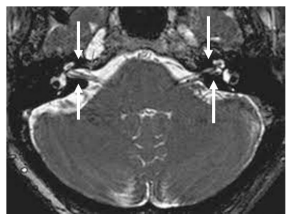

Observe a imagem a seguir:

É possível afirmar que trata-se do seguinte exame: